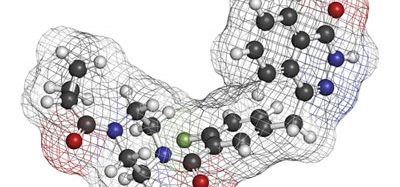

Target-based approaches to drug discovery have traditionally sought compounds of high binding affinity to the drug target. Affinity of inhibitory compounds is classically assessed using a labeled ligand which is competed from binding to the drug target. The important attributes of the inhibitory compound are its IC50 evaluated from inhibitor dose-response curves and its dissociation constant of binding, Ki as calculated from this empirical data using the Cheng-Prusoff equation, knowing the concentration of labeled ligand used in the assay and its equilibrium dissociation constant, Kd.

However, in recent years drug target kinetics has become an alternate method of evaluating inhibitors rather than the thermodynamic approach as outlined above. In these assays, the reciprocal of the inhibitor off rate, 1/koff, or the inhibitor residence time on the drug target, computed with the Motulsky and Mahan equation, becomes the important attribute. Various studies have shown that drug residence times are a promising early stage indicator of in vivo drug activity.